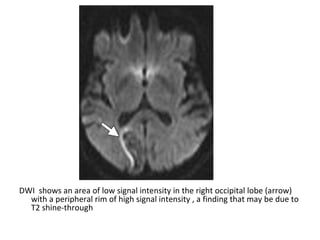

DWI shows an area of low signal intensity in the right occipital lobe (arrow)

with a peripheral rim of high signal intensity , a finding that may be due to

T2 shine-through

ADC map shows a corresponding area of high signal intensity

(arrow)

T1 shows a corresponding area of low signal intensity (arrow)

T2 shows an area of high signal intensity in the right occipital

lobe (arrow)

T1+C shows a corresponding area of parenchymal enhancement